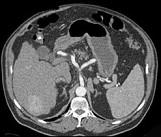

问题 男,44岁,患乙肝多年,现腹痛,腹胀,AFP增高,消瘦、乏力,影像检查如图,最可能诊断是 ( )

选项 A.肝血管瘤 B.肝腺瘤 C.肝转移瘤 D.肝硬化、肝癌 E.肝结节性增生

答案 D